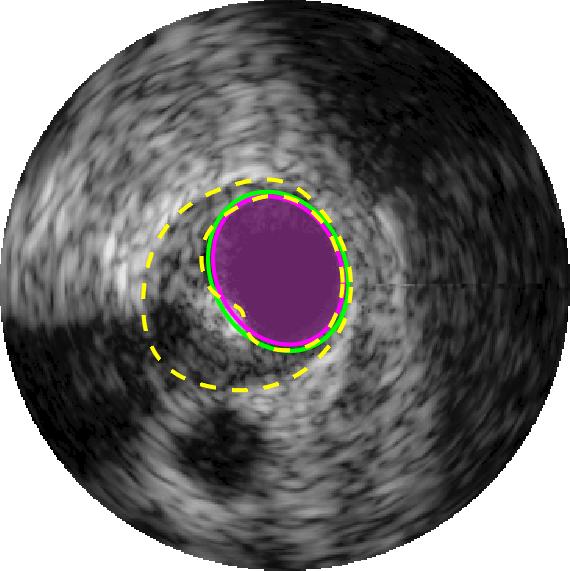

Qualitative evaluations are illustrated in Figure 4 and show the successful segmentation results of the proposed EREL selection strategy for 20 IVUS frames. The lumen areas are highlighted by the magenta colour while the media regions are green. Also, the manually annotated contours for both lumen and media are drawn as yellow dashed lines. As we can see, the chosen frames contain a variety of lumen and media morphologies.